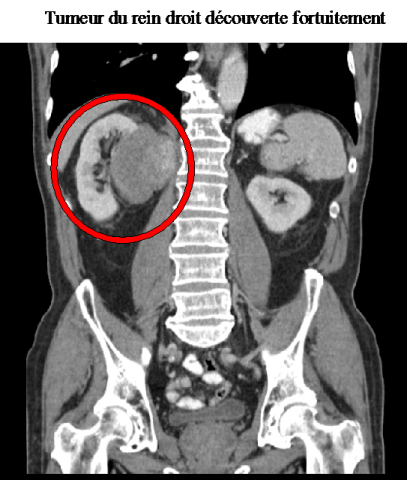

Le cancer du rein grandit généralement en ne donnant que peu fréquemment des symptômes. Il est souvent diagnostiqué de manière fortuite, à l’occasion d’un examen radiologique abdominal (scanner ou échographie). Comme ces examens sont très souvent utilisés par les médecins aujourd’hui plus de 50% des cancers sont diagnostiqués à un stade très localisé et donc guérissables.

tumeur du rein droit découverte fortuitement: